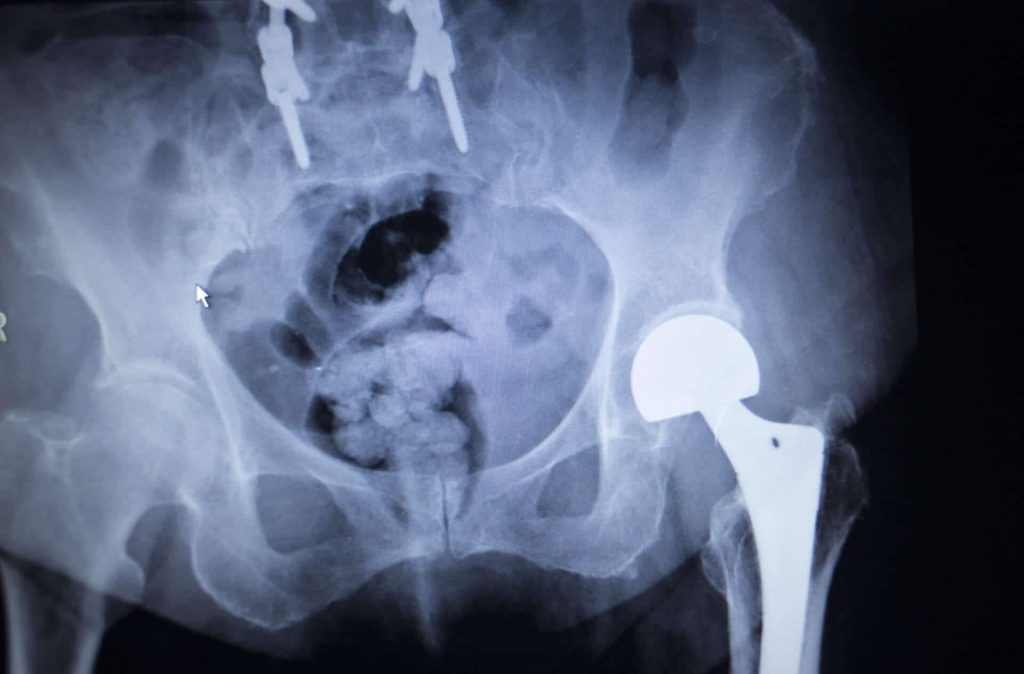

Lawsuits have been filed against Stryker Orthopaedics after it issued a voluntary recall for the Stryker ABG II hip, Stryker Rejuvenate, LFIT Anatomical CoCr V40 Femoral Head, and Tritanium Acetabular Shell devices, prompted by reports of excessive metal debris and ion generation. Stryker’s metal-on-metal implants are made from different metal alloys for enhanced strength.

However, these defective implants do not function properly, resulting in serious complications for many patients, such as pain, inflammation, loss of mobility, infection, dislocation, blood clots, and metal ions being absorbed into the bloodstream. Patients have filed lawsuits against Stryker Corporation to receive compensation for additional revision surgery, treatment, and other medical bills.

Most of the problems associated with Stryker Rejuvenate and ABG II modular-neck joint hip stem systems are related to the metal neck components in the implants made of cobalt, chromium, and titanium.

Due to the modular neck design of the Stryker hip implant, the friction caused by the regular movement of these metal-on-metal Stryker hip replacement systems sheds metallic debris into the blood, leading to metal poisoning as well as the following problems:

Metallosis is caused when cobalt and chromium ions are released into the bloodstream and surrounding tissue, causing metal poisoning. Common symptoms of metallosis can include painful inflammation, tissue and bone death, severe pain, and systemic issues, such as problems with the kidney and heart. It can also cause severe symptoms like vision loss, hearing loss, cognitive impairment, and heart failure.

Defective implants become unreliable over time and may cause dislocations, leading to mobility issues for the patient.

Chemical reactions people have from the metal debris going into the surrounding tissue can lead to adverse local tissue reactions, like necrosis, osteolysis (bone degeneration, which can lead to broken bones), and pseudotumors near the site of the implant.